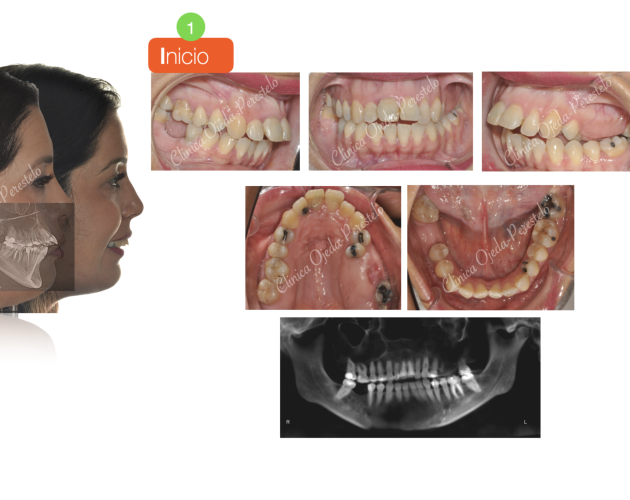

Caso Multidisciplinar: Ortodoncia- Coronas sobre Implantes Casos de Éxito - Adultos - Casos Multidisciplinares